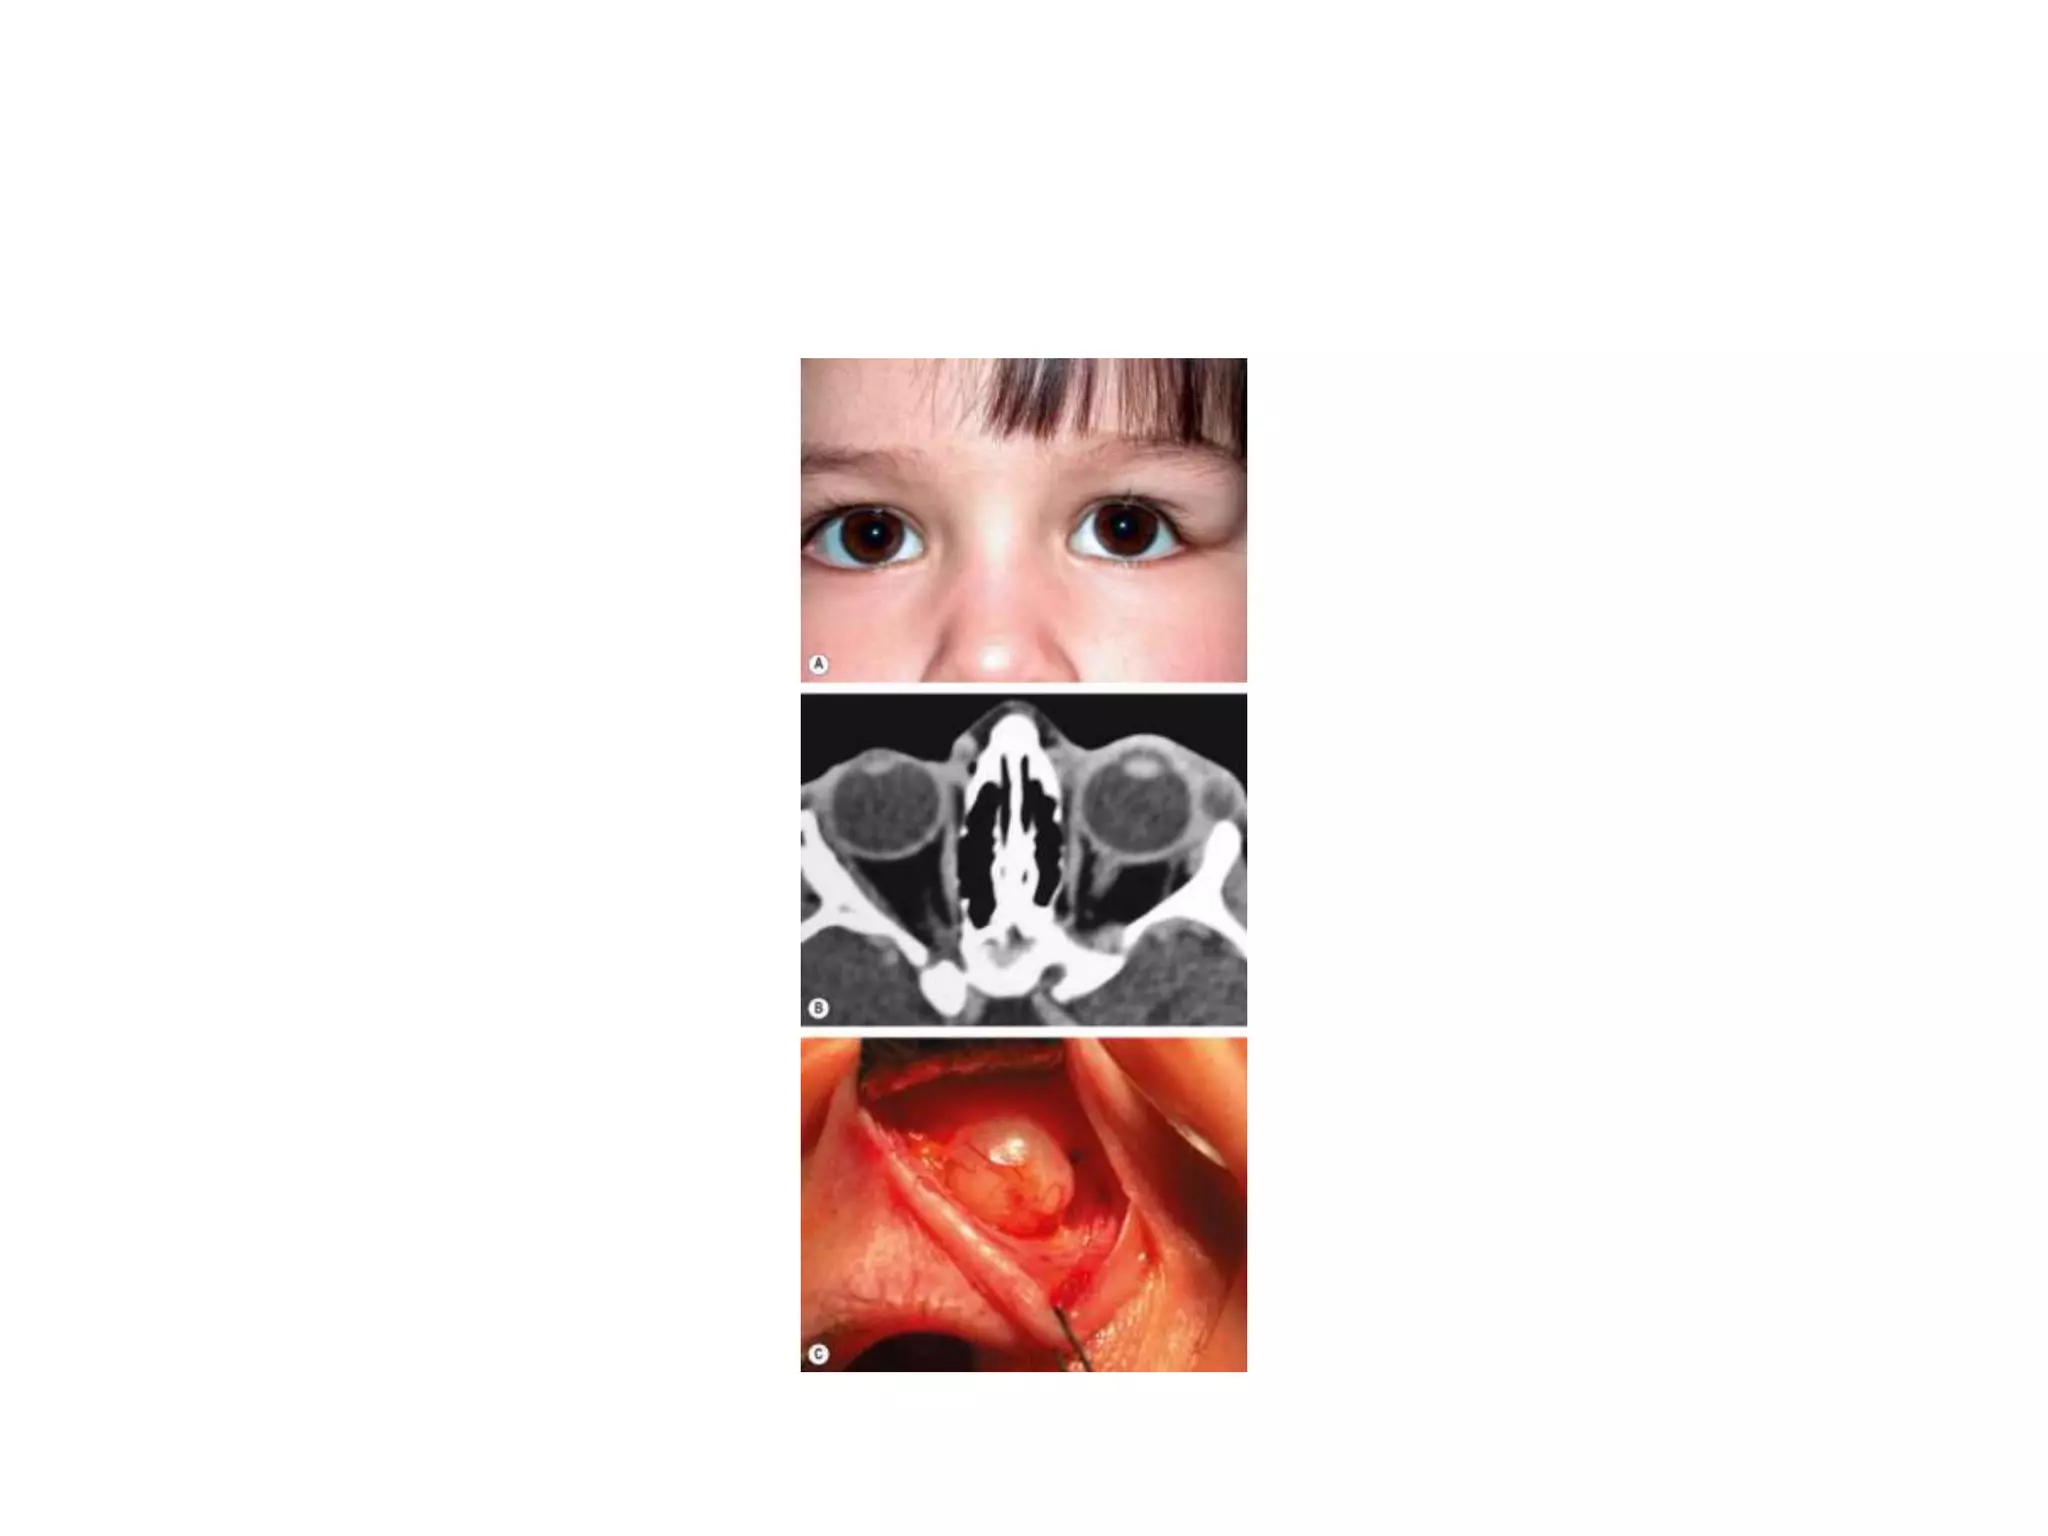

ENCEPHALOCELE

• An encephalocele is formed by herniation of

intracranial contents through a congenital defect

of the base of the skull.

• A meningocele contains only dura whilst a

meningoencephalocele also contains brain tissue.

• Orbital encephalocele may be (a) anterior (fronto-ethmoidal)

or (b) posterior, which is associated

with dysplasia of the sphenoid bone.

• Presentation is usually during infancy.

• SIGNS:

• Anterior encephaloceles involve the superomedial

part of the orbit and displace the globe forwards

and laterally.

• Posterior encephaloceles displace the globe

forwards and downwards .

• The displacement increases on straining or crying

and may be reduced by manual pressure.

• Pulsating proptosis may occur due to

communication with the subarachnoid space but,

because the communication is not vascular, there is

neither a thrill nor a bruit.

• CT shows the bony defect responsible for the

herniation.

ENCEPHALOCELE • Anencephalocele is formed by herniation of intracranial contents through a congenital defect of the base of the skull. • A meningocele contains only dura whilst a meningoencephalocele also contains brain tissue. • Orbital encephalocele may be (a) anterior (fronto-ethmoidal) or (b) posterior, which is associated with dysplasia of the sphenoid bone.

• 15.

• Presentation isusually during infancy. • SIGNS: • Anterior encephaloceles involve the superomedial part of the orbit and displace the globe forwards and laterally. • Posterior encephaloceles displace the globe forwards and downwards . • The displacement increases on straining or crying and may be reduced by manual pressure. • Pulsating proptosis may occur due to communication with the subarachnoid space but, because the communication is not vascular, there is neither a thrill nor a bruit.

• 16.

• CT showsthe bony defect responsible for the herniation. • Differential diagnosis • a Of anterior encephaloceles includes other causes of medial canthal swellings such as dermoid cysts and amniontoceles of the lacrimal sac. • b Of posterior encephaloceles includes other orbital lesions that present during early life such as capillary haemangioma, juvenile xanthogranuloma, teratoma and microphthalmos with cyst.